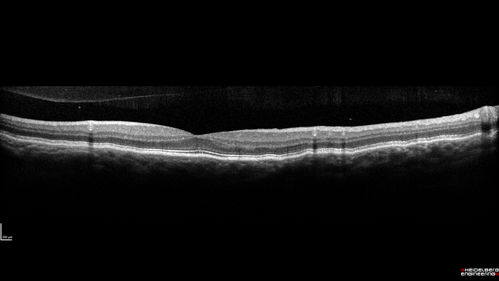

Nanophthalmous with Choroidal Folds

71 year old female with 20/20 vision and worsening cataracts. There is also a CHRPE lesion in the periphery